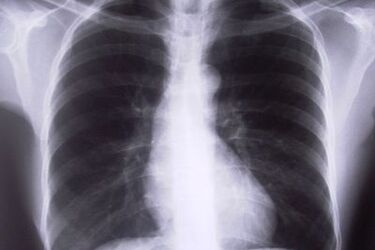

Siedemdziesiąt sześć podlaskich gmin odwiedzi nowy ambulans białostockiego Szpitala Gruźlicy i Chorób Płuc.

W ramach projektu zostanie wykonanych 14 tysięcy badań RTG klatki piersiowej i 4 tysiące badań spirometrycznych. Zapewniony zostanie również bezpłatny dowóz wytypowanych już pacjentów z okolicznych miejscowości. Główną grupą docelową są przede wszystkim osoby ze środowisk patologicznych, gdzie występuje największe prawdopodobieństwo zachorowania na gruźlicę. Jednak planuje się przebadanie wszystkich osób, które zgłoszą się na badania z niepokojącymi objawami. Zakup specjalnego ambulansu i badania zostały sfinansowane ze środków Mechanizmu Finansowego Europejskiego Obszaru Gospodarczego oraz Norweskiego Mechanizmu Finansowego. Projekt potrwa do września. źródło: Wrota Podlasia